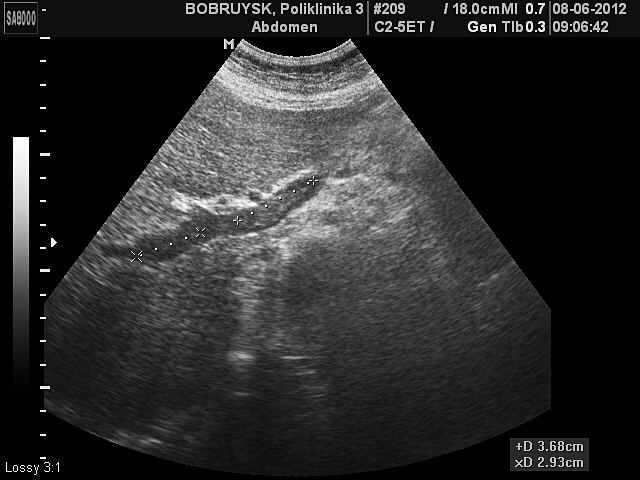

Женщина 62 лет.

Неполный тромбоз воротной вены и ее ветвей

Причин данного тромбоза не знаю, т.к пациентка пришла только с предыдущим УЗИ и результатами ангиографии с Минска.

Ни карточки ни выписки на руках не было.

Сослов пациентки, проходит амбулаторное лечение тромболитиками, рекомендовано УЗИ в динамике, по месту жительства и консультации по графику в Минске.